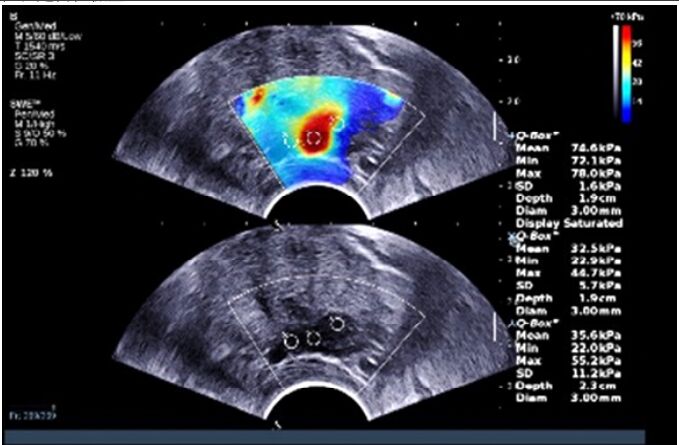

70.經直腸前列腺超音波呈現低回音病兆在左後 peripheral zone,下圖 color map 及定量測量(以 kPa 為單位)是何種檢查?

(A)都卜勒超音波(Doppler Ultrasound) (B)超音波彈性造影(ultrasound elastography) (C)對比劑超音波造影(contrast-enhanced ultrasound) (D)M-mode 超音波